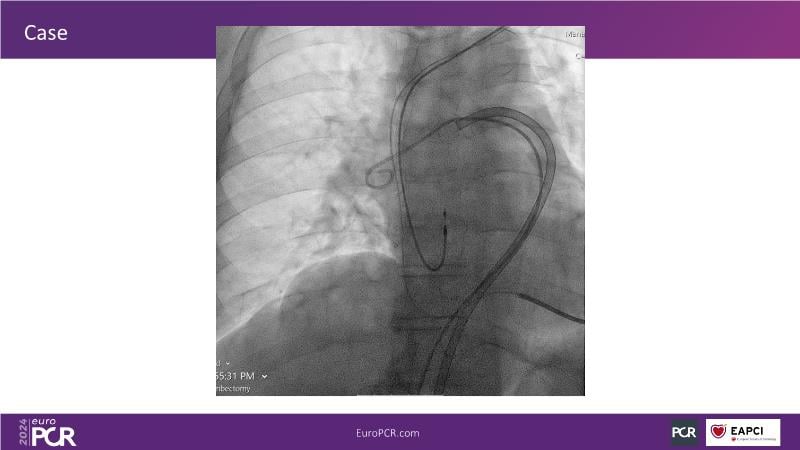

Advancing percutaneous treatment of pulmonary embolism with computer-assisted vacuum thrombectomy

Join this session to delve into innovations in computer-assisted vacuum thrombectomy for acute pulmonary embolism, leveraging real-life case scenarios to share practical experiences and discuss treatment strategies. Amidst the current surge in scientific research, ongoing trials like STORM PE and STRIKE PE are pivotal in shaping the landscape of pulmonary embolism management.